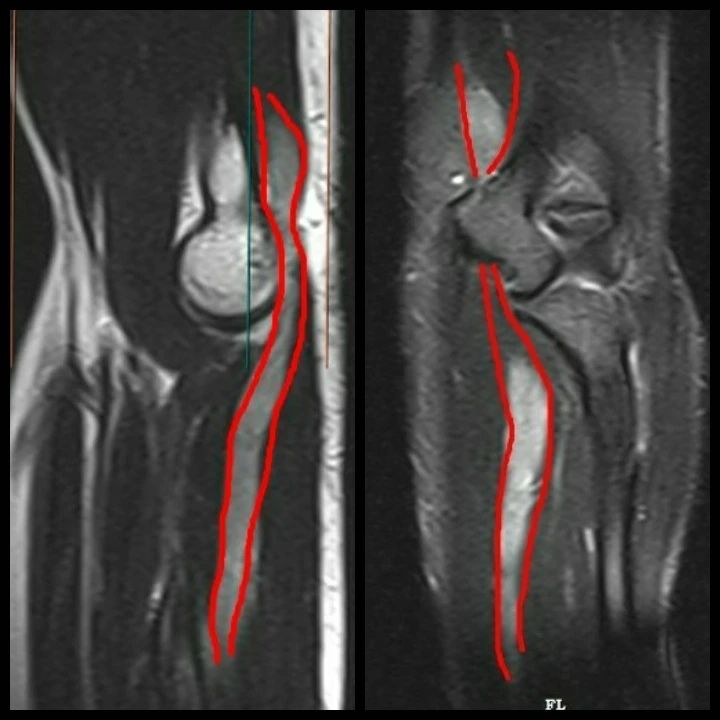

Marked long segment fusiform thickening of the ulnar nerve over an approximate length of 17 cm extending from the level of distal humeral metaphysis to distal ulnar diaphysis (The distal extent is not completely imaged in this study) – *represents ulnar neuropathy , of concern for infective etiology, likely leprosy versus plexiform neurofibroma*

Ulnar neuropathy , of concern for infective etiology, likely leprosy versus plexiform neurofibroma